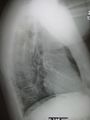

Normal lateral CXR

A lateral CXR showing right lower lobe pneumonia